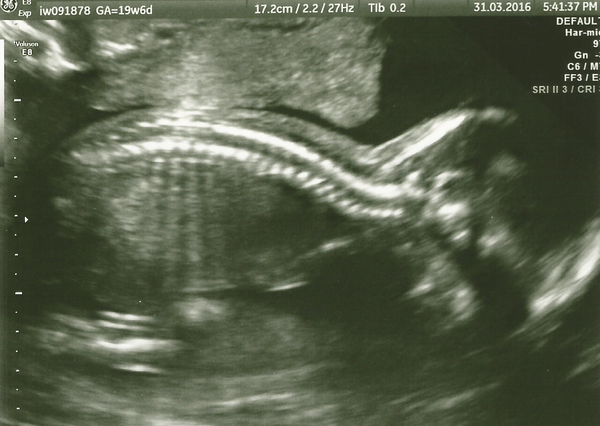

I too had my 20 week scan yesterday and my little one was quite happy to show off the goods! Typical boy flashing it around. My kids and the baby's dad all came with me so I let them choose the three pictures. 7 year old son asked the sonographer for a photo of the bits! Fortunately she said no lol Everything else was all good. Here is a bump picture too, taken two weeks ago at 18 weeks, pretty sure he's going to be a big one, one foot was measured yesterday at 3cm !!